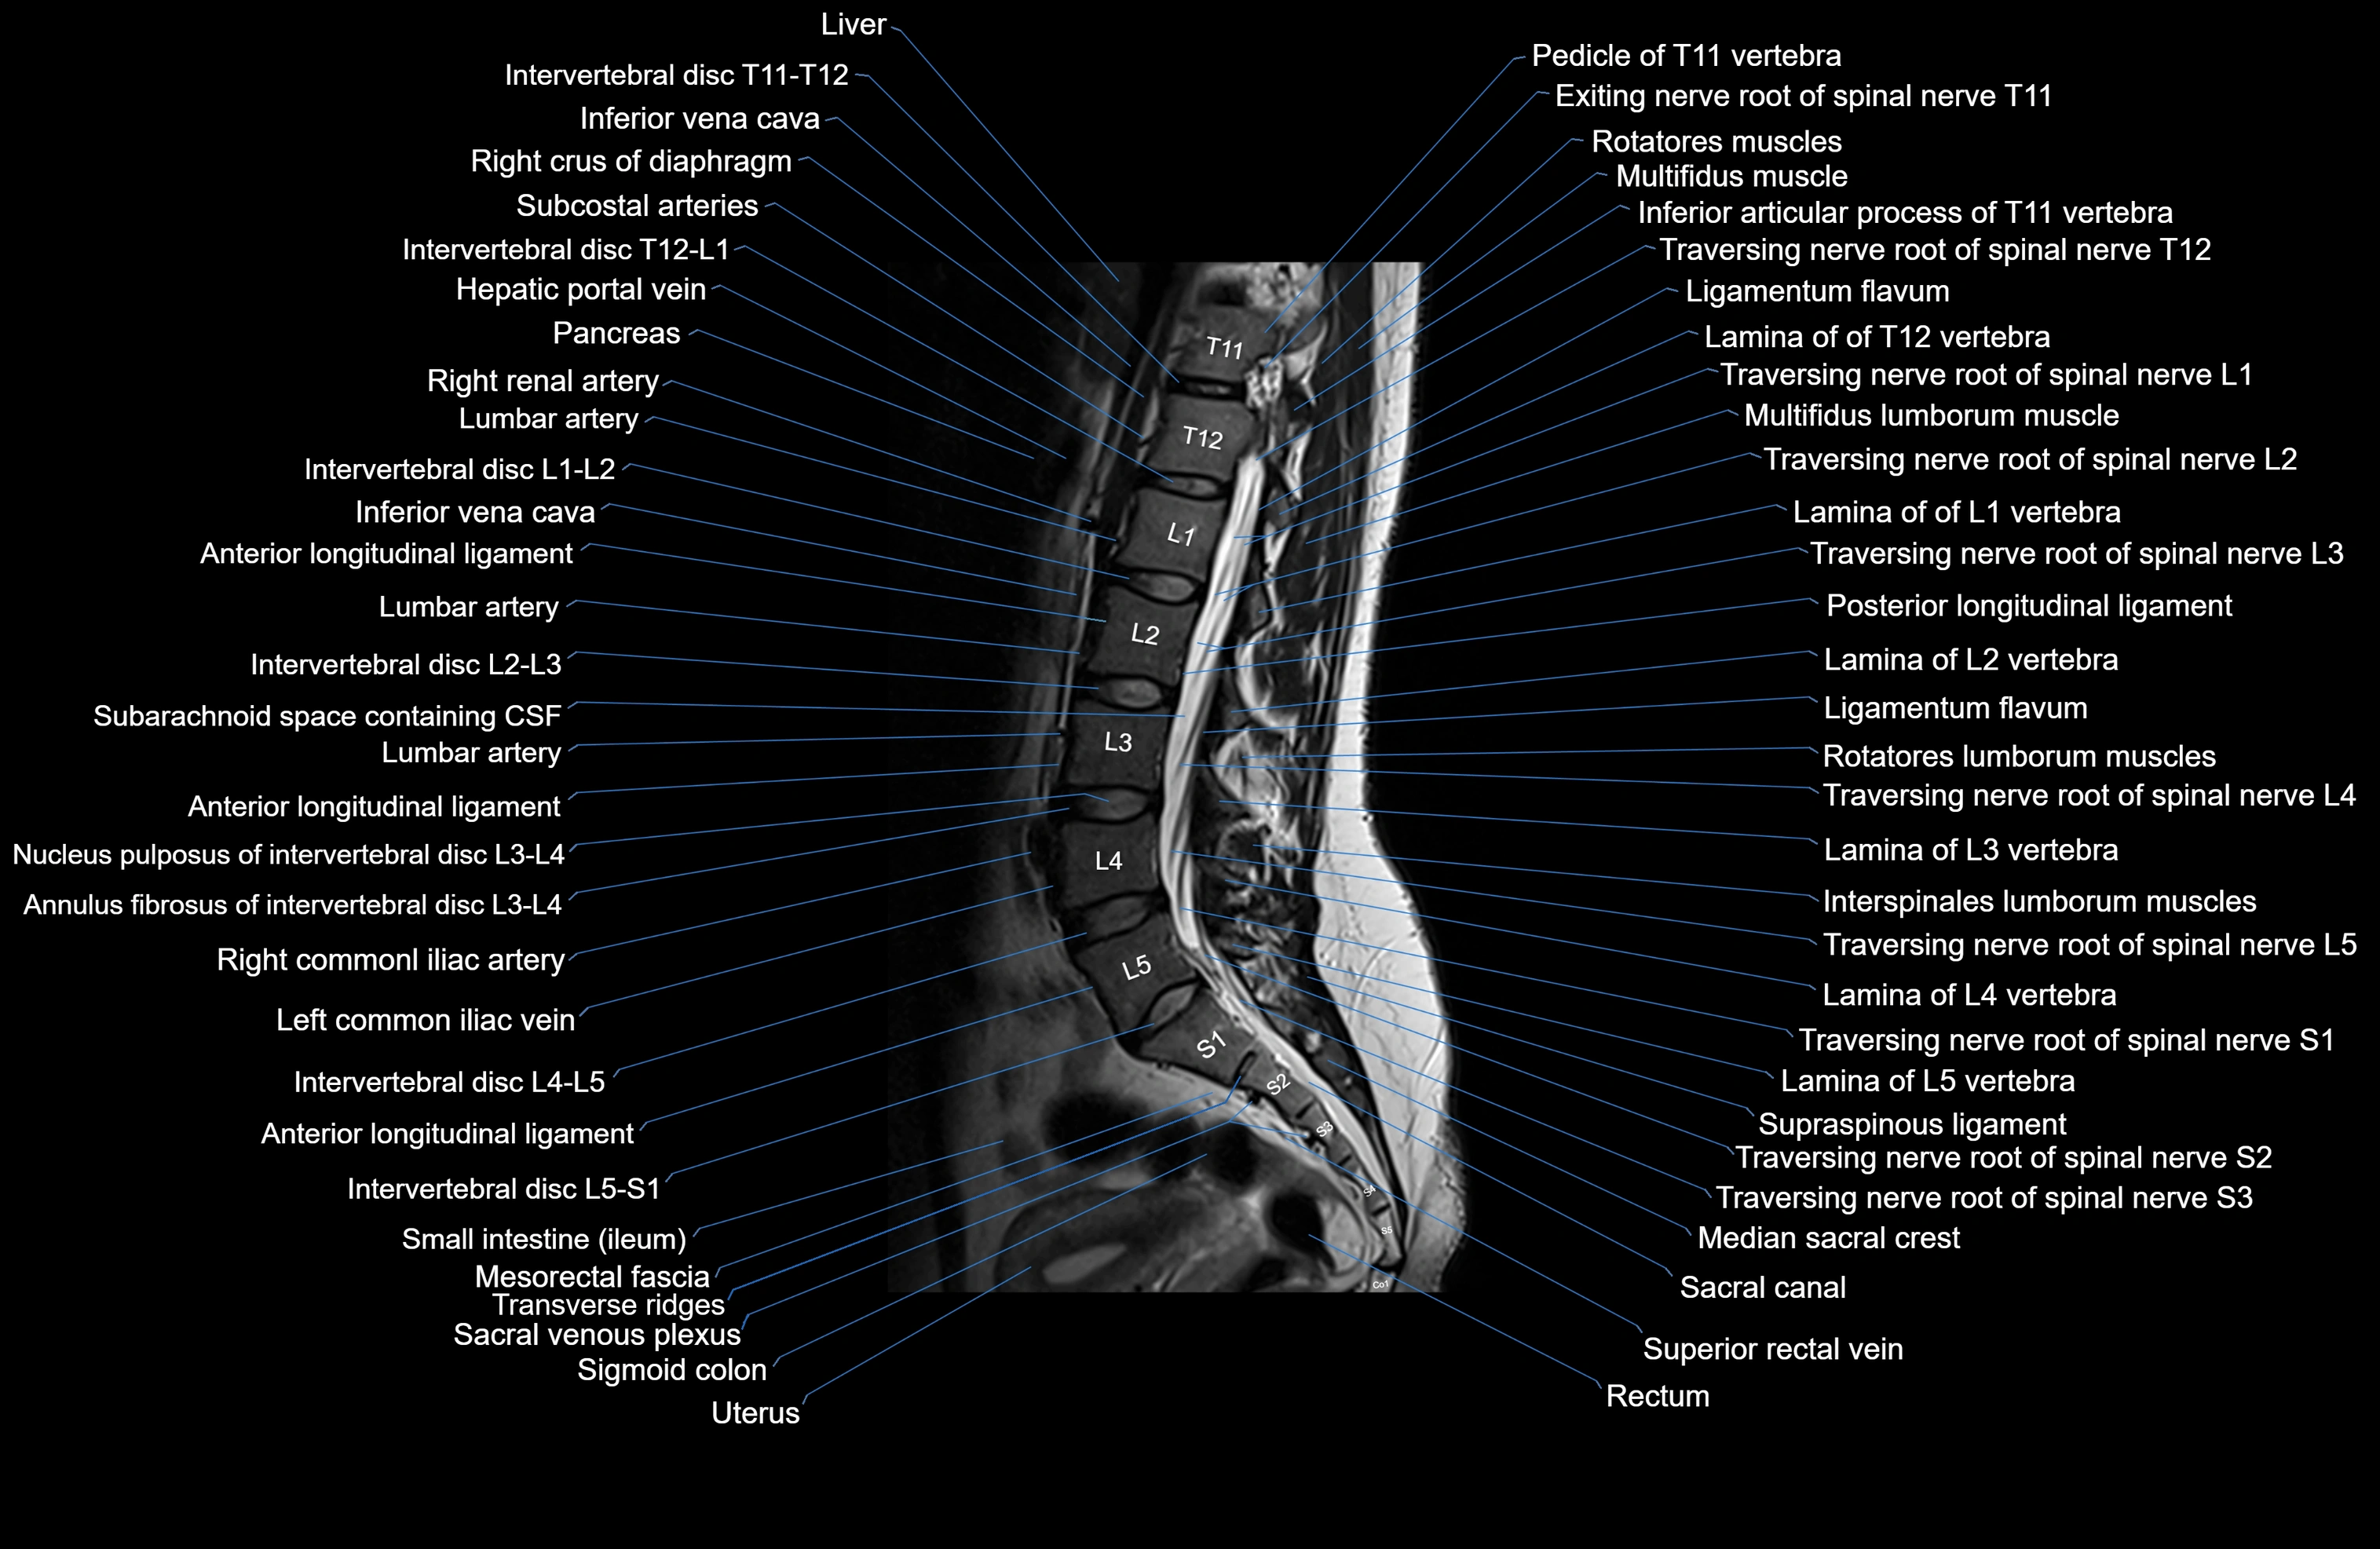

MRI images